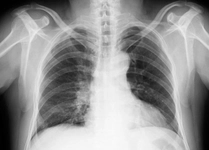

Temiz akciğer tomografisi, akciğerlerde anormal bulguların olmadığını gösteren önemli bir görüntüleme sonucudur. Bu sonuç, akciğer sağlığının iyi olduğunu ve olası hastalıkların tespit edilmediğini belirtir. Ancak, kesin tanı için sağlık profesyoneli ile görüşmek gereklidir.

Temiz Akciğer Tomografisi Ne Anlama Geliyor?Günümüzde tıpta tanı ve tedavi süreçlerinde önemli bir yer tutan görüntüleme yöntemlerinden biri olan akciğer tomografisi, hastalıkların teşhisinde kritik bir rol oynamaktadır. "Temiz akciğer tomografisi" ifadesi, genellikle akciğerlerde herhangi bir anormal bulguya rastlanmadığı anlamına gelir. Bu bağlamda, temiz bir akciğer tomografisi sonucu, hastanın akciğer sağlığının iyi olduğunu gösterir. Akciğer Tomografisi Nedir?Akciğer tomografisi, yüksek çözünürlüklü görüntüler elde etmek için X-ray teknolojisini kullanan bir görüntüleme yöntemidir. Bu yöntem, akciğerlerin iç yapısının detaylı bir şekilde incelenmesine olanak tanır. Tomografi, akciğerlerdeki lezyonlar, tümörler, enfeksiyonlar ve diğer patolojilerin tespit edilmesinde son derece etkili bir yöntemdir. Temiz Akciğer Tomografisi SonucuTemiz bir akciğer tomografisi sonucu, şu durumları ifade edebilir:

Bu sonuç, genellikle hastanın akciğer sağlığının iyi olduğunu ve herhangi bir ciddi patoloji olmadığını gösterir. Ancak, bu sonuçlar her zaman kesin bir tanı anlamına gelmez; doktorun klinik değerlendirmesi ve hastanın genel sağlık durumu da göz önünde bulundurulmalıdır. Temiz Akciğer Tomografisinin ÖnemiTemiz akciğer tomografisi sonucu, özellikle kronik akciğer hastalığı, kanser riski veya enfeksiyon öyküsü bulunan hastalar için büyük bir rahatlık kaynağıdır. Bu durum, hastaların tedavi süreçlerine olumlu yönde katkı sağlar ve gereksiz endişeleri azaltır. Ayrıca, temiz bir tomografi sonucu, sağlık profesyonellerine hastanın durumu hakkında daha fazla bilgi verir ve gelecekteki muayene ve tedavi planlamalarına yardımcı olur. SonuçTemiz akciğer tomografisi, akciğer sağlığının iyi olduğunu gösteren önemli bir bulgudur. Ancak, bu sonucun değerlendirilmesi için mutlaka bir sağlık profesyoneliyle görüşülmesi gerektiği unutulmamalıdır. Her durumda, kişinin genel sağlık durumu, belirtiler ve diğer tetkiklerin sonuçları birlikte ele alınmalıdır. Sağlıklı bir yaşam tarzı, düzenli kontroller ve zamanında yapılan tetkikler, akciğer sağlığının korunmasında önemli rol oynamaktadır. |